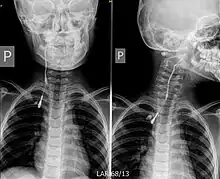

Fistulogram (sinogram) of a right branchial cleft sinus.